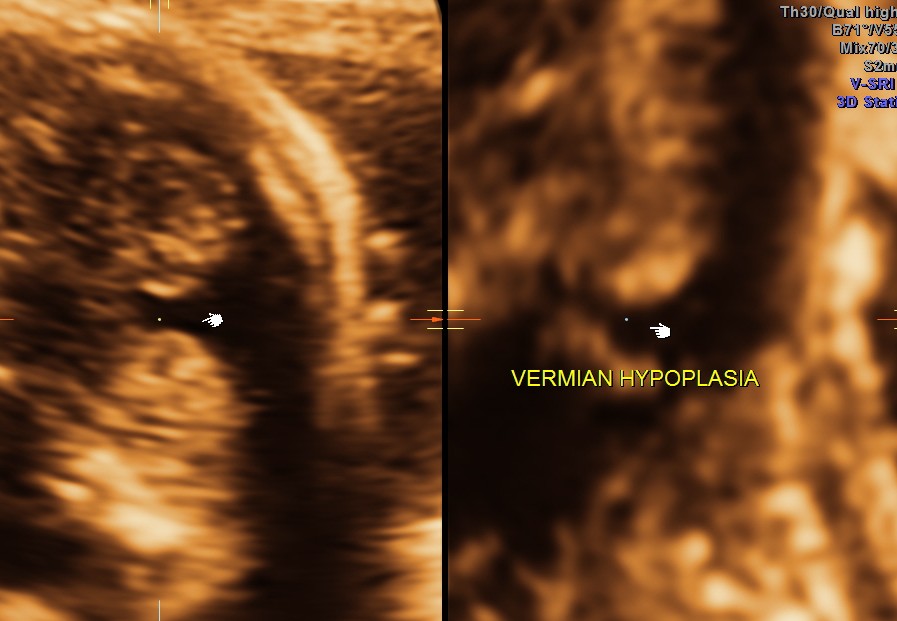

Ultrasound pictures of the fetal cranium are given below and showed cerebellar vermian dysgenesis .The buttocks sign can be appreciated.